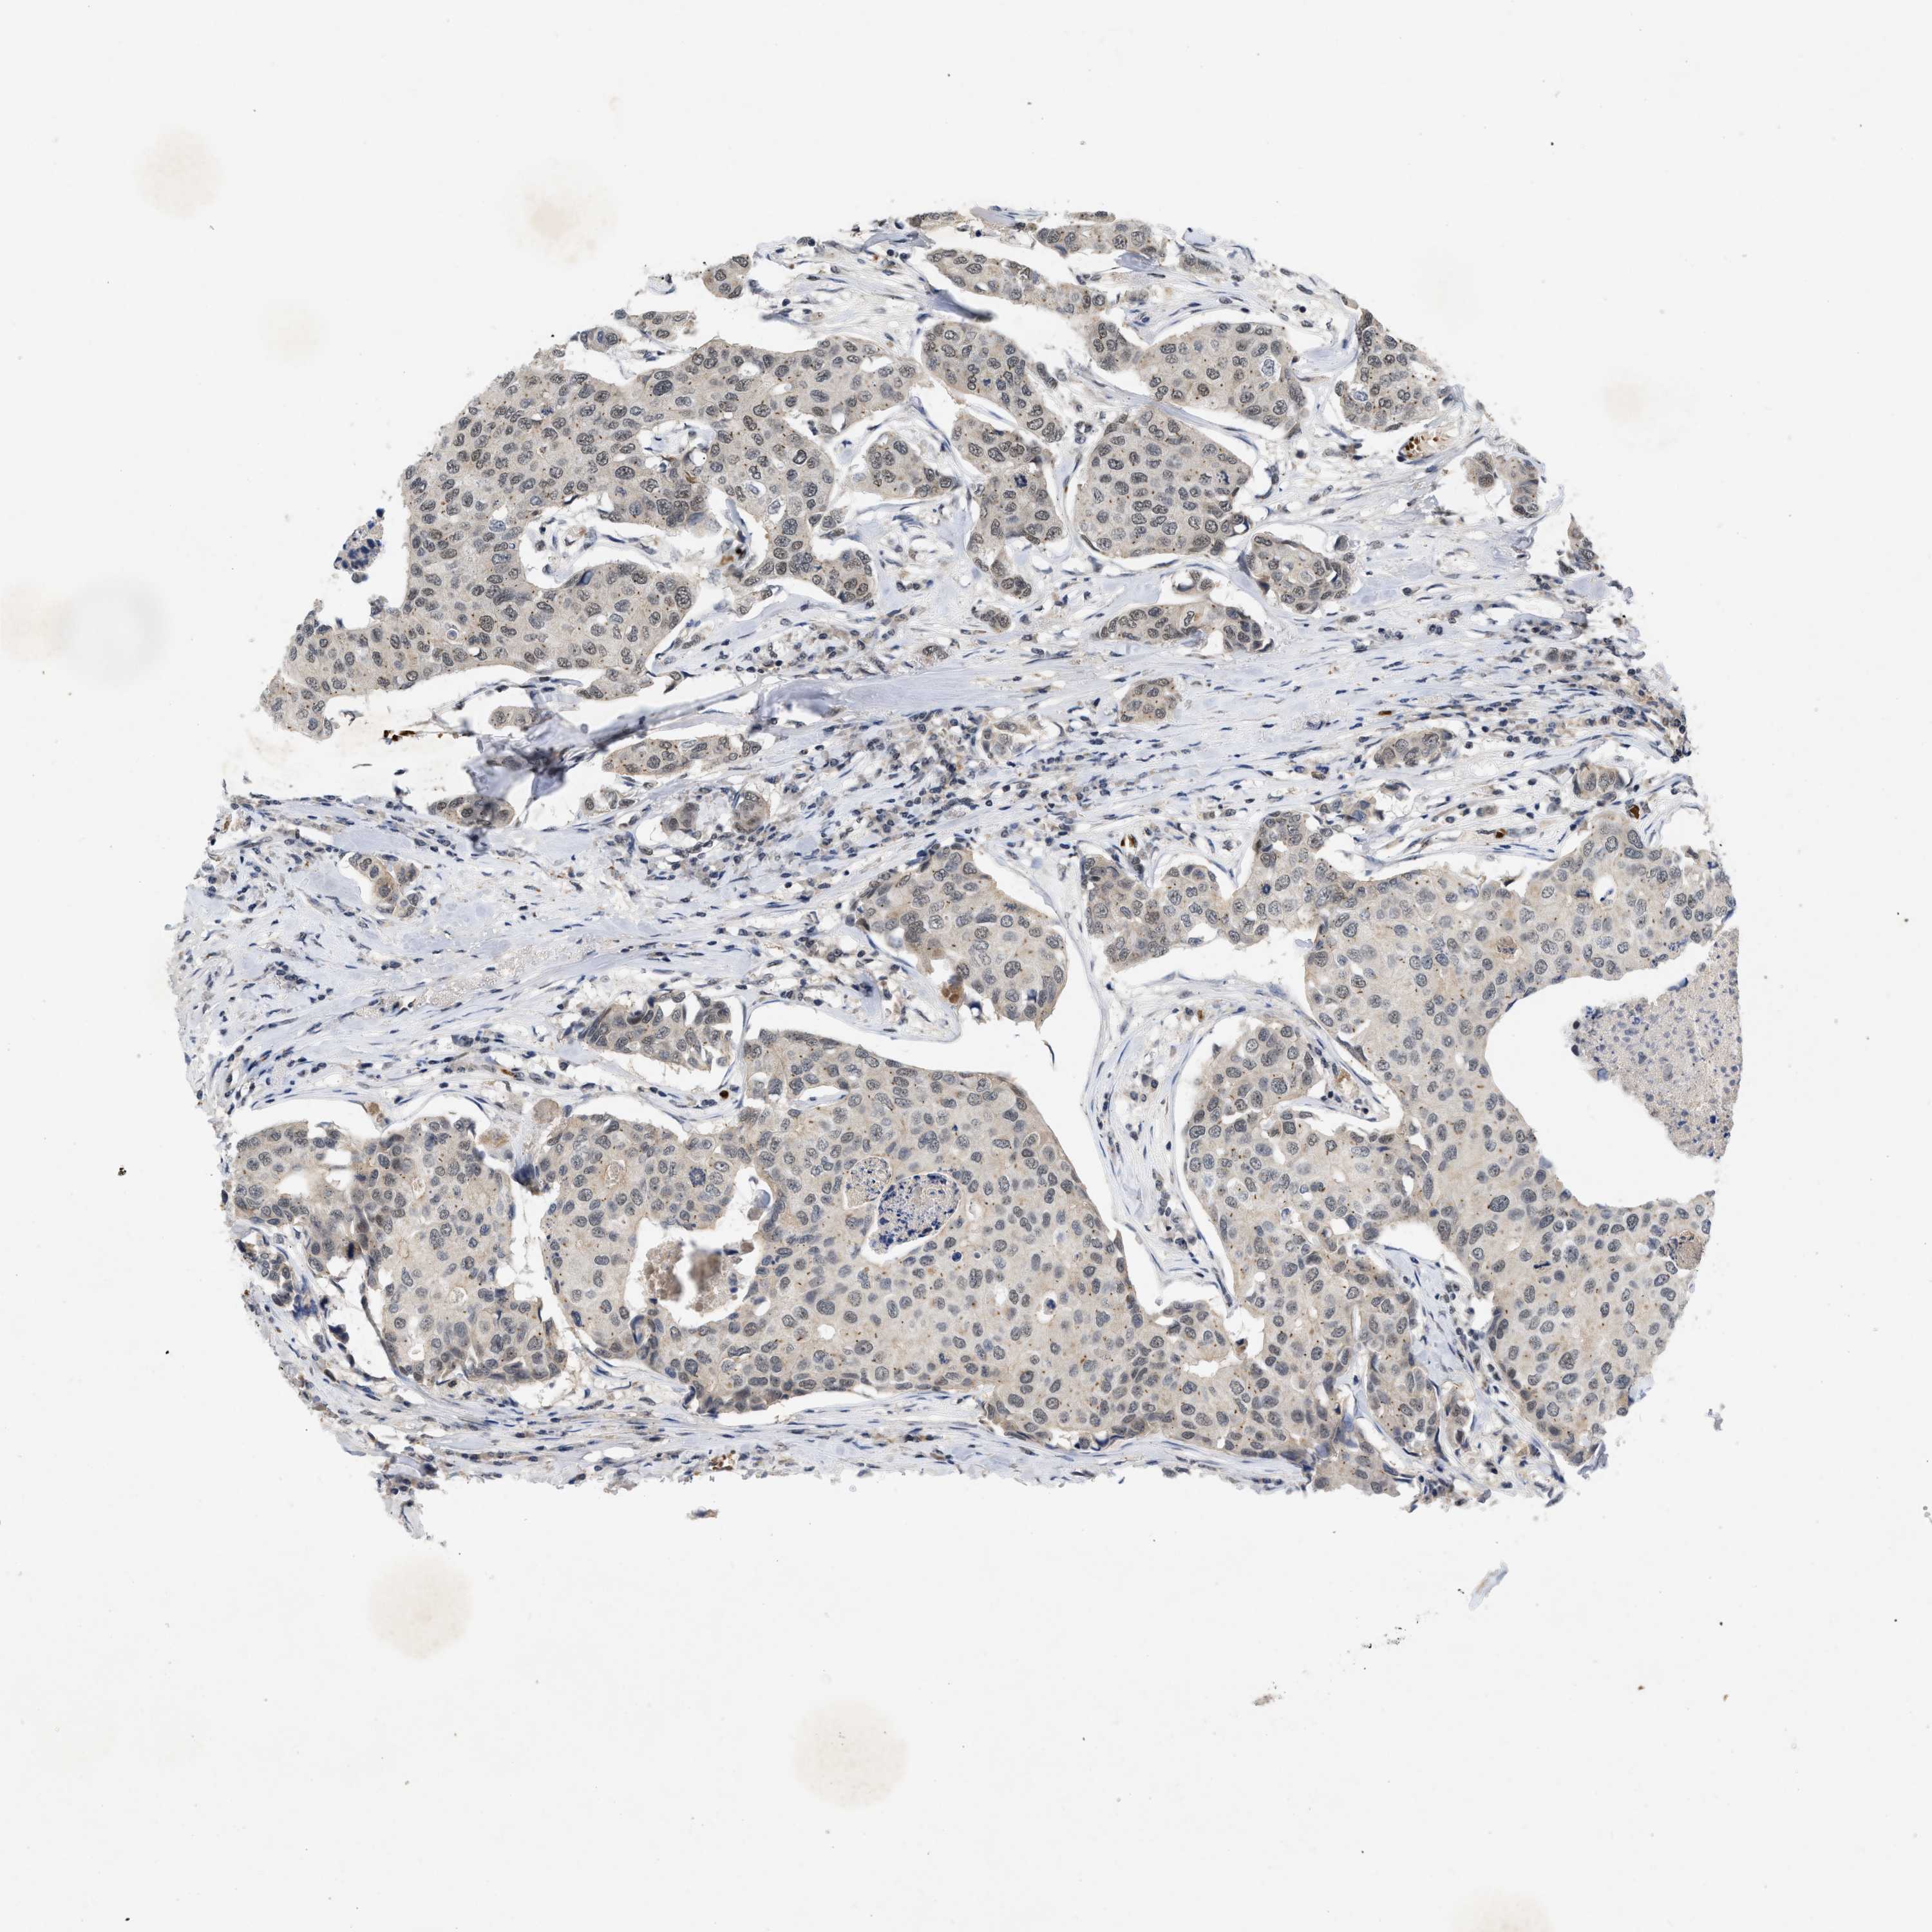

BRCA TCGA BRCA VALIDATION PROTEIN EXPRESSION